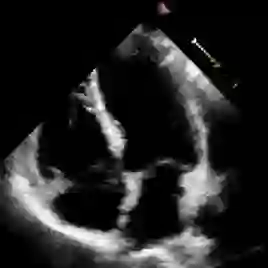

Accurate and consistent predictions of echocardiography parameters are important for cardiovascular diagnosis and treatment. In particular, segmentations of the left ventricle can be used to derive ventricular volume, ejection fraction (EF) and other relevant measurements. In this paper we propose a new automated method called EchoGraphs for predicting ejection fraction and segmenting the left ventricle by detecting anatomical keypoints. Models for direct coordinate regression based on Graph Convolutional Networks (GCNs) are used to detect the keypoints. GCNs can learn to represent the cardiac shape based on local appearance of each keypoint, as well as global spatial and temporal structures of all keypoints combined. We evaluate our EchoGraphs model on the EchoNet benchmark dataset. Compared to semantic segmentation, GCNs show accurate segmentation and improvements in robustness and inference runtime. EF is computed simultaneously to segmentations and our method also obtains state-of-the-art ejection fraction estimation. Source code is available online: https://github.com/guybenyosef/EchoGraphs.